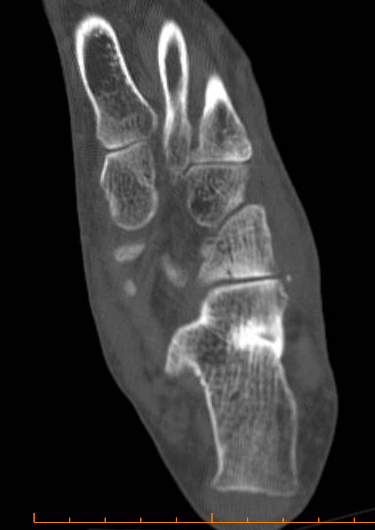

ÄÄÇ»ÅÍ ÃÔ¿µ : Á¾°ñÀÇ °ñÀý , µÎ ºÎÀ§(÷ºÎ ÆÄÀÏ Âü°í)

ÄÄÇ»ÅÍ ÃÔ¿µ ÆÇµ¶¿¡¼­ Á¾°ñÀÇ µÎ ºÎÀ§ °ß¿­°ñÀýÀÌ ¾ð±ÞµÇ¾úÁö¸¸ ÃÊÀ½ÆÄ°Ë»ç»ó  Ãß°¡ÀûÀÎ °ñÀýÀ»

È®ÀÎÇÒ ¼ö ÀÖ¾ú´Ù.

ÄÄÇ»ÅÍ ÃÔ¿­»óÀÇ °ñÀý ºÎÀ§´Â ÃÊÀ½ÆÄ°Ë»ç¿¡¼­ È®ÀÎÇÒ ¼ö ÀÖ¾ú°í »çÁø 10~15¿¡¼­ È®ÀÎÀÌ °¡´ÉÇÏ´Ù.